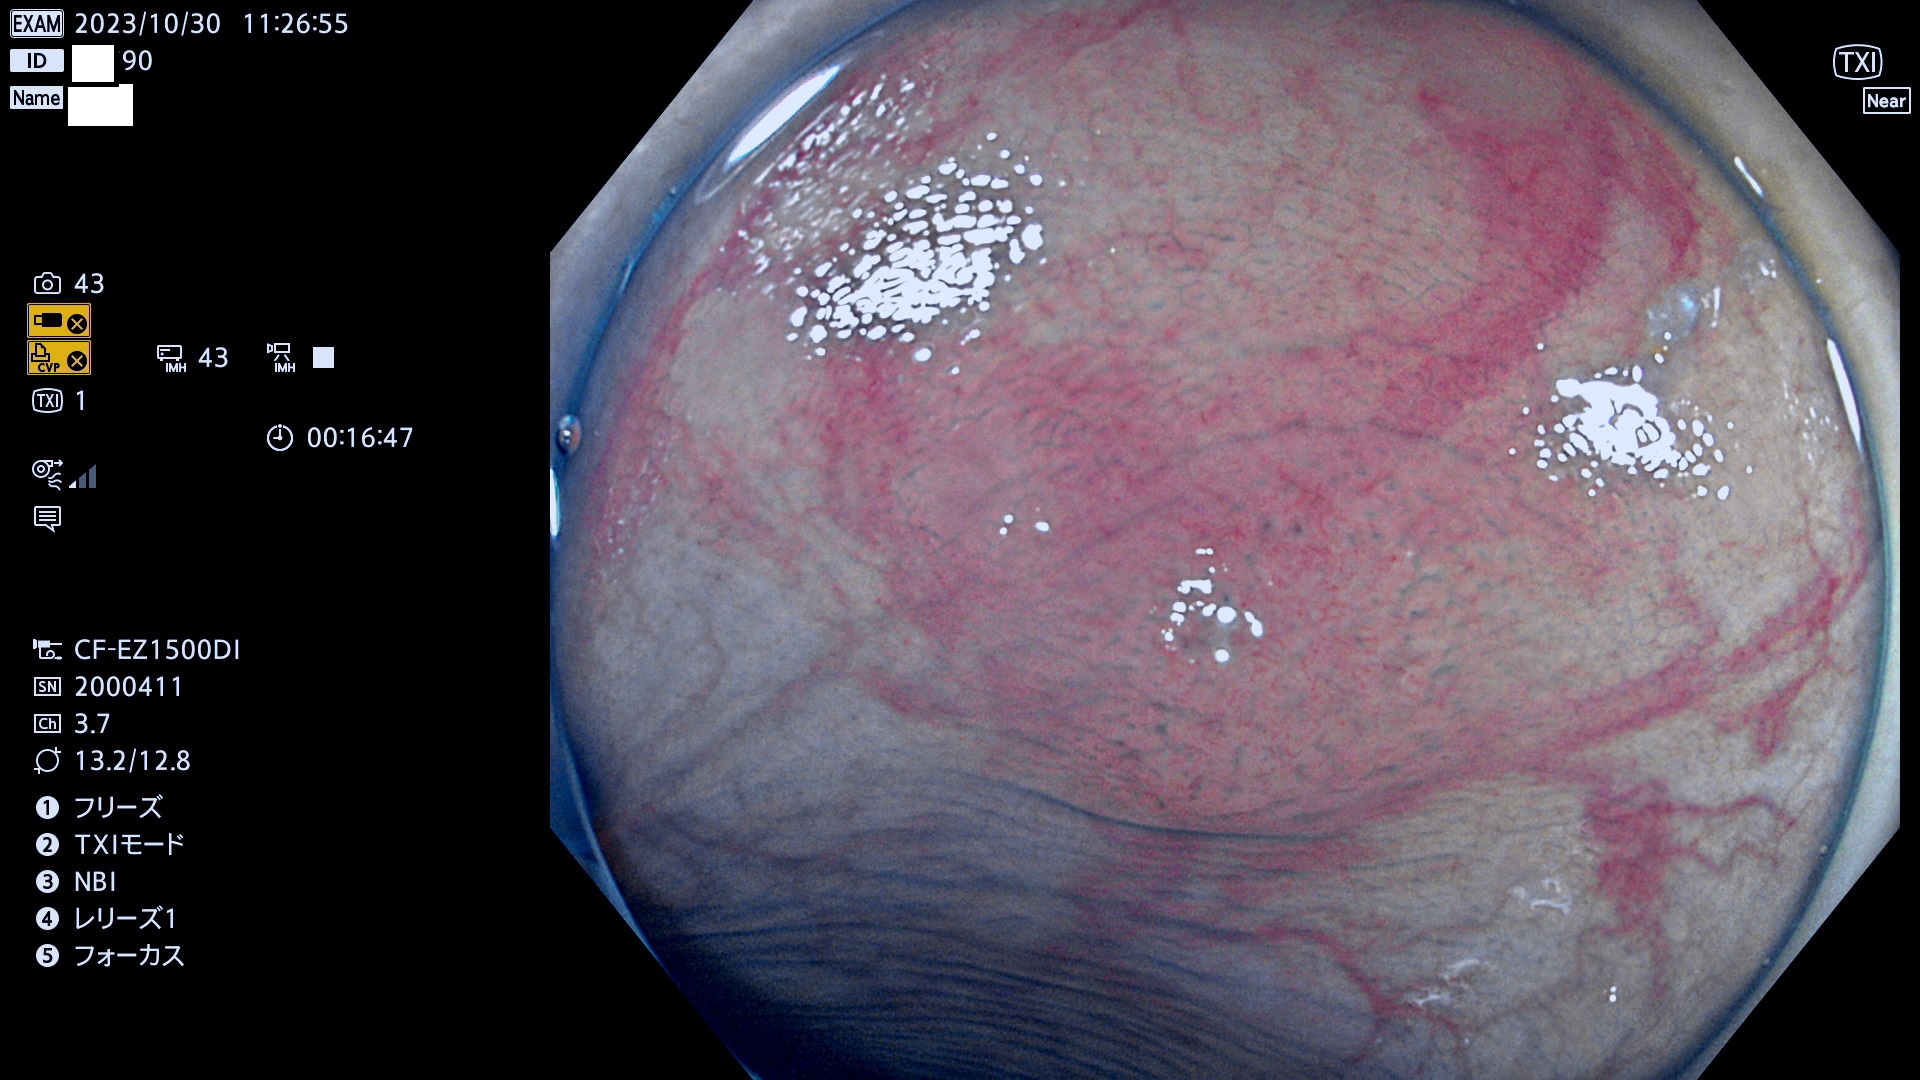

表面型腺腫(Flat Adenoma)の中で、完全に平坦な物をUb、陥凹している物をUcと呼びます。平坦隆起型(Ua)よりも、発見が難しく危険な病変です。このタイプは「内視鏡後・大腸癌の重要犯人」であり、この発見率は「腺腫発見率」よりも、重要な意味があります。

毎週の検査(木・金・土・日)に発見されたUb、Uc型・腺腫を、その週の日曜の夜にUPし1週間、提示します。

抽出の対象期間 2023年10月26日(木)〜10月30(月)の5日間(60件の検査)7件